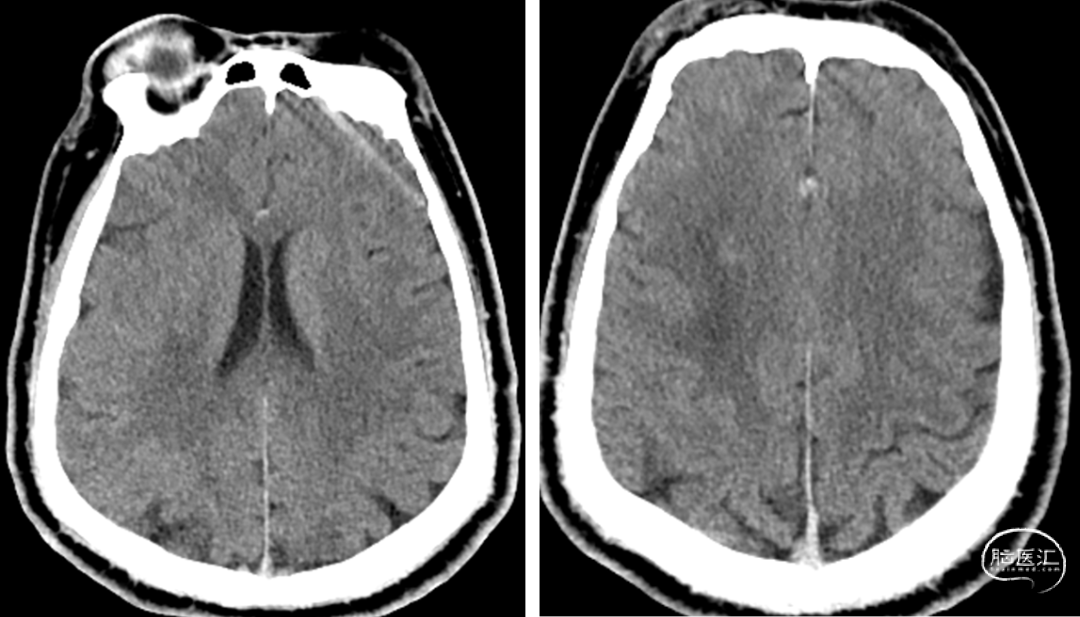

MR提示:右侧半卵圆区新发脑梗死(A、B)。

头颅CTA提示:右侧大脑中动脉M1段闭塞;左侧椎动脉V4段重度狭窄(C、D)

头颅CTP:右侧大脑中动脉区域明显低灌。

脑血管造影:右侧大脑中动脉M1段闭塞,代偿不足。

左椎动脉V4段重度狭窄。

术前行高分辨率核磁共振:右侧大脑中动脉前壁强化斑块。

术后CT无出血,术后患者未诉不适,无新发神经功能症状及体征,继续予以抗栓、强化降脂、调节血糖等治疗。